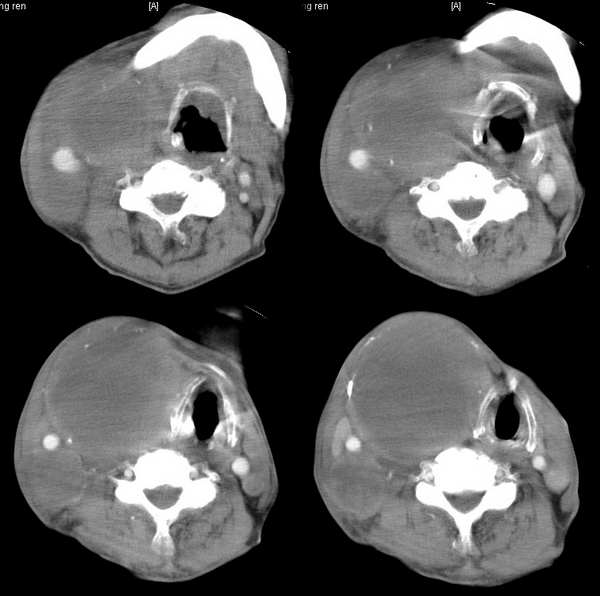

男,74岁,甲状腺肿30余年。现右颈部出现新肿块,疼痛,感乏力。

右颈部巨大软组织肿块影,范围较广,上至下颌角,下至颈静脉切迹。其最大层面位于右侧甲状腺区。肿块密度不均,其中有坏死液化区和班片状钙影,增强扫描见肿块实质区有强化。邻近结构挤压移位,部分结构侵蚀破坏,右侧多个颈深淋巴结肿大。两肺弥漫分布小结节影,以胸膜下为主,其大小不等,边缘光整。右侧胸壁亦见软组织结节影,纵隔多个淋巴结肿大及两侧锁骨上淋巴结肿大。

意见:右侧甲状腺癌并两肺、胸壁、纵隔淋巴结、颈深淋巴结、锁骨上淋巴结等广泛转移。